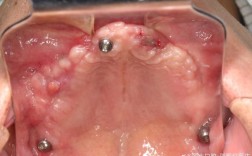

(图片来源网络,侵删)- 下牙槽神经损伤: 在下颌后牙区种植时,种植体位置过深或偏离,可能损伤下牙槽神经,导致下唇、下巴区域出现麻木、感觉异常或刺痛,虽然大部分是暂时性的,少数情况下可能是永久性的。

(图片来源网络,侵删)- 极其罕见,通常发生在严重骨质疏松、骨量严重不足且医生操作不当的情况下。